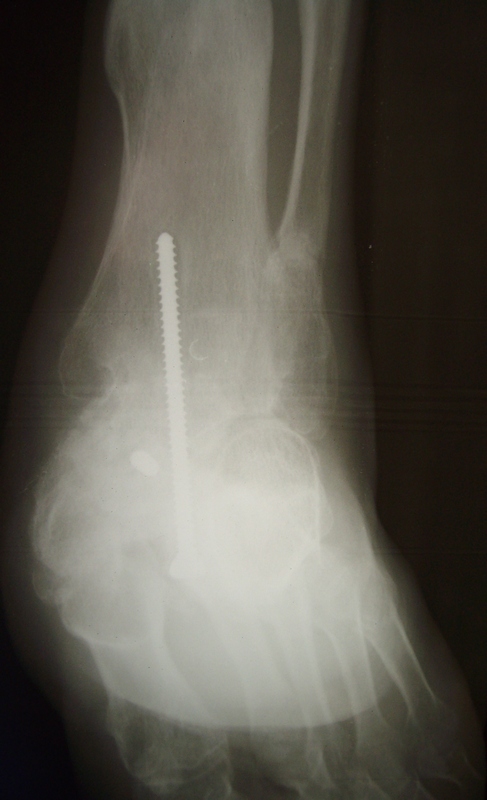

Лечился по поводу перелома D- 12 позвонка с нижним парапарезом и оскольчатых переломов плюсневых костей левой стопы. Производился остеосинтез переломов плюсневых костей левой стопы спицами.В 2007 году произведена стабилизирующая операция на позвоночнике с ламинэктомией и фиксацией металлоконструкцией и операция артродез левого голеностопного, подтаранного, таранно-ладьевидного, межклиновидных суставов с фиксацией винтами. В 2008 г. часть винтов удалена. Больной отмечает появление парестезий и движений в пальцах обеих стоп в этом году ( ежедневно пользуется миостимулятором Аб Троник).В настоящее время жалобы на деформацию и нестабильность в левой стопе, боль в области голеностопного сустава, в области пятки (проекция винта).

При осмотре имеется плоско-вальгусная деформация левой стопы, болезненность в пяточной области в проекции винта, тугоподвижность в области шопарова сустава. На тыльной поверхности рубцы. План лечений: удаление винта с подошвенной области, корригирующий реартродез в щопаровом суставе. Как удалить остатки винта? Возможно, понадобится реартродез голеностопного или подтаранного сустава.

In 2007 stabilizing operation on a backbone with laminectomy and arthrodesis of ankle,subtalar, talo-navicular, intecuneiform joints with fixing by screws . In 2008 the part of screws is removed. The patient marks{celebrates} occurrence movements in fingers of both stop in this year.

Now patient complains to deformation and instability in left stop, a pain in the area of ankle joint and in the field of a heel (a projection of the screw).

At survey there is valgus and planus a deformation of left foot, morbidity in calcaneal area in a projection of the screw,the motion in the midfoot. There is the hems on a back surface of foot.

Здравствуйте!Мы в таких случаях удаляем металл.А затем устраняем с некоторой гиперкоррекцией(3-5гр),имеющиеся деформации стопы.В этом случае-приведение переднего отдела,отведение среднего,ротацию пятки,пронацию переднего отдела,вальгус пятки и эквинус стопы(примерно видно по снимкам).Так же по R-гр. видно ,что можно справиться закрыто(точнее после повторных R-гр).Работаем с аппаратами Илизарова.Фиксация 3мес.Со второго дня(п\о период)обучаем нормальной ходьбе с учетом биомеханики.